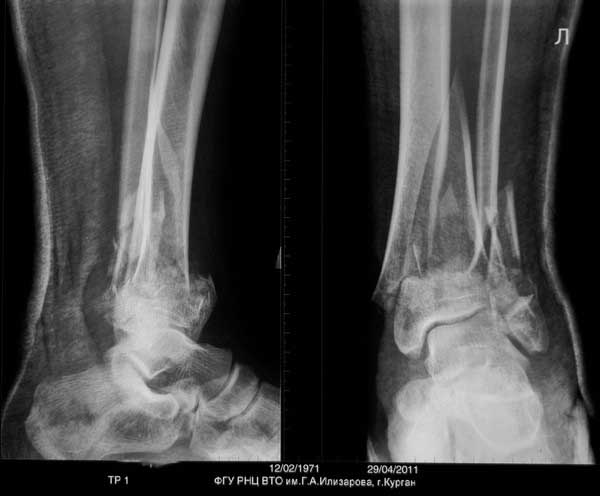

Судя по р-грамме, по имеющимуся "облачку" на медиальной стороне, идет консолидция отломков.

Так что - только открытое, одномоментное выправление. Осторожненько поработайте распатором, освобождая от мозоли (лучше используйте круглый распатор Кобба!) и медленно растягивайте на дистракционном ортопедическом столе, под контролем ЭОП-а.

По поводу голени, вариант "улучшить стояние костных отломков" открытым методом - немного рискованно, потому что результат манипуляции "распатором Кобба" с дескелетизацией фрагментов скажется немедленно. Для предупреждения осложнений и будущих дисскуссий “как победить сегментарную дефект”, желательно работать без интервенции на начавшийся репаративный процесс с максимальным сохранением костной мозоли.

Для максимального сохранения консолидации сверху мозоли можно согнуть пластину, но это крайняя мера и не обязательно подгонять показания под имеющийся имплантат. Если не удовлетворяет положение, или неполная консолидация, вместо пластины можно применить отечественный аппарат Илизарова. Спросите у докторов Соломина или Мацукатова, и они подскажут методы исправления деформации собственными "гексаподами".

Для оценки степени сращения костей голени рекомендуется сделать КТ срезы. И возможно, для голени не надо предпринимать ничего. Там процесс консолидации заканчивается, и хотя форма далека от идеала, но не так уж плоха. Уже время для нагрузки, и дайте возможности нагружать! Время покажет, и в зависимости от активности в дальнейшем можно обсудить план лечения в будущих дисскуссиях.